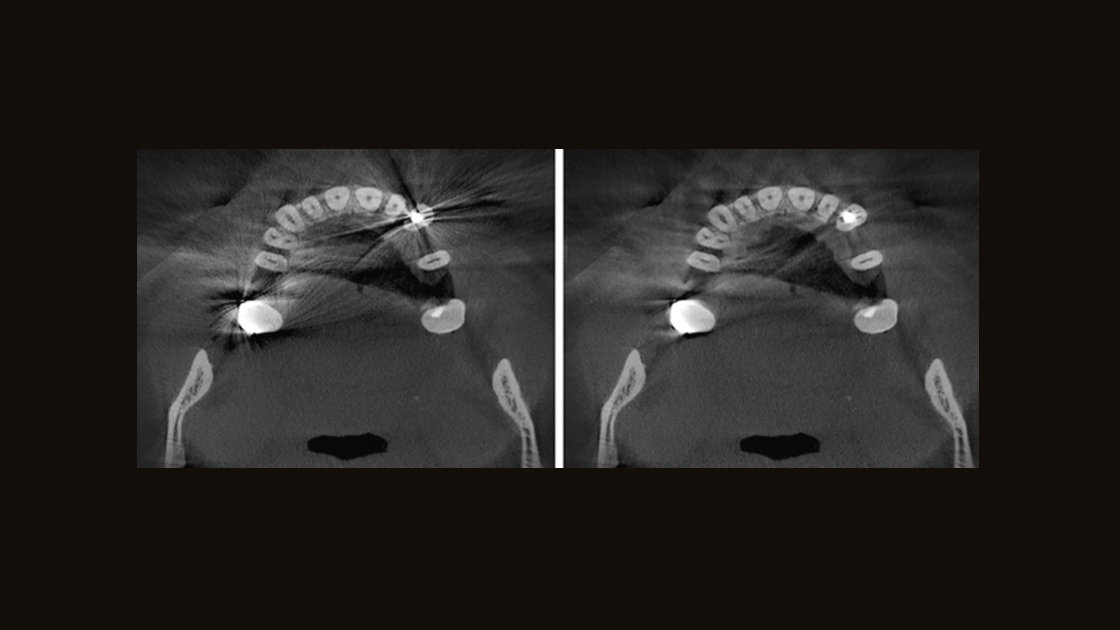

Improve the oral health of your patients by having the ability to diagnose and plan treatment for nearly all etiology in the dentomaxillofacial region. DS X-ray solutions support patient needs from capturing the temporomandibular joints to visualizing the smallest details using up to 80 µm high-resolution endodontic X-ray.

When combined with DS Core capabilities and robust X-ray software, Dentsply Sirona customers have the confidence they need to deliver better patient care.